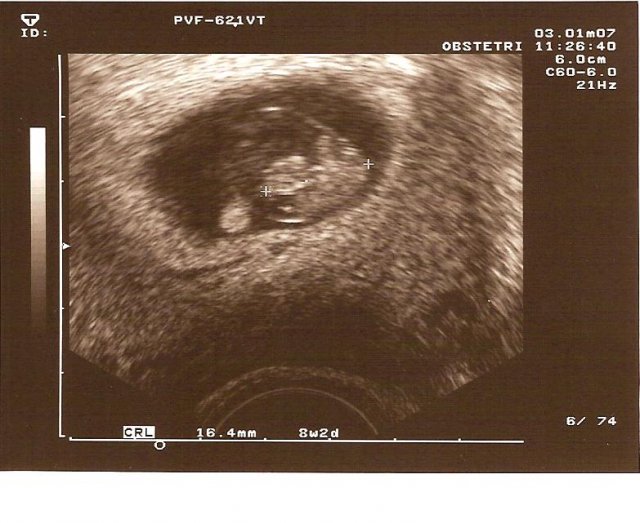

Nase prvni manzelske dny jsou opravdu romanticke a porad vzpominame...